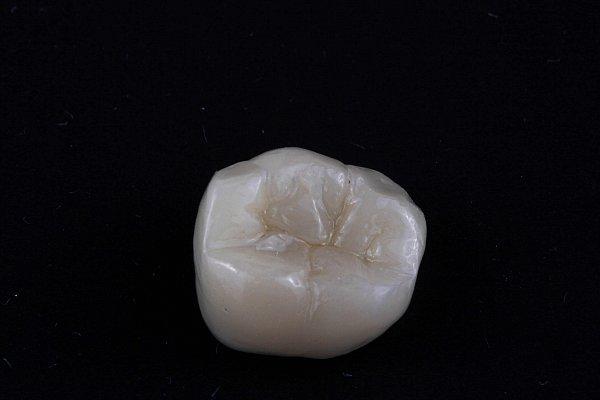

Пациентка 30 лет. Жалоба на скол зуба 36.

Исходная ситуация — обширное разрушение зуба.

Результат: установлена керамическая коронка